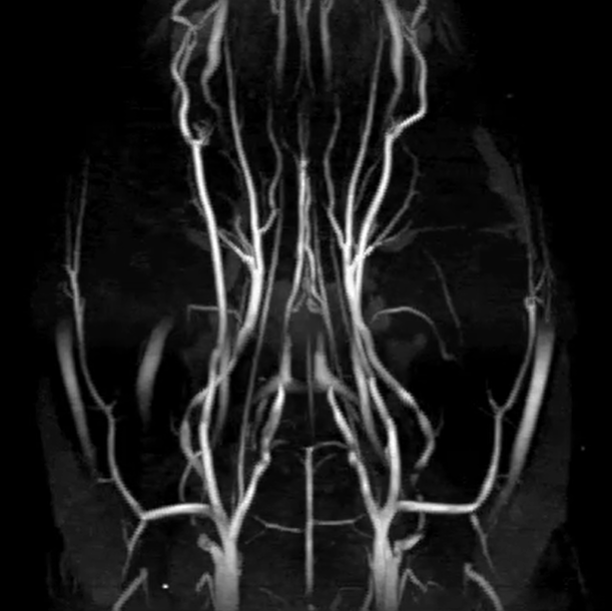

3T高分辨率TOF磁共振成像技术

使用美迪索 42毫米大鼠脑射频线圈,无需任何造影剂即可获取卓越质量的ToF MRA图像。即使在3T的条件下,大脑前动脉(ACA)、大脑中动脉(MCA)和威利斯环(CoW)也清晰可见。

〉动物模型:Wistar大鼠

〉序列:

二维飞行时间磁共振血管成像(2D ToF MRA),

平面分辨率:107微米,

切片厚度:100微米, 视场:32毫米×30毫米×28毫米,

TR(回波时间):70毫秒,

TE(回波消除时间):5.7毫秒

〉线圈: 42毫米正交大鼠脑线圈和专用脑成像室